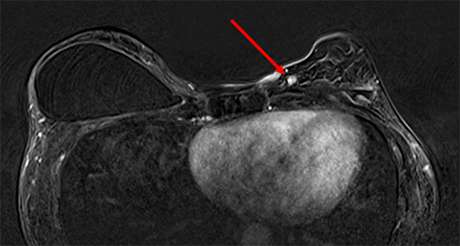

Focus is defined by BI-RADS as abnormal enhancement measuring less than 5mm in diameter that is too small to characterize and cannot be categorized as a mass or non-mass enhancement (1) (Figure 1). Abnormal enhancement describes an area that enhances above the background parenchymal enhancement on contrast-enhanced MRI sequences (2). Kinetics are a useful adjunct in breast MRI for further characterizing enhancing lesions, however, the small size of foci (< 5 mm) may limit kinetic analysis due to partial volume averaging. Partial volume averaging is a phenomenon that occurs when a lesion is below the resolution of the imaging modality.

Figure 1. T1 fat-saturated postcontrast axial subtraction MRI demonstrating an enhancing focus in the left breast at 11 o’clock anterior depth.

Why are foci important in breast MRI? Because they can be malignant (3). Reports in the literature provide a very broad range of estimated risk of malignancy (3-6%), therefore, these findings are often characterized as BI-RADS 3 – likely benign and short-term follow-up is recommended. In the event that a focus increases in size, is new, or demonstrates washout kinetics, then it could be assigned a BI-RADS 4 – suspicious – and a biopsy (likely MR-guided biopsy) would be warranted. In some cases, enhancing foci may be categorized as BI-RADS 2 – benign – if they have features specific to benign lesions (i.e. cyst, fat necrosis, lymph node, apocrine metaplasia, and myxoid fibroadenoma).